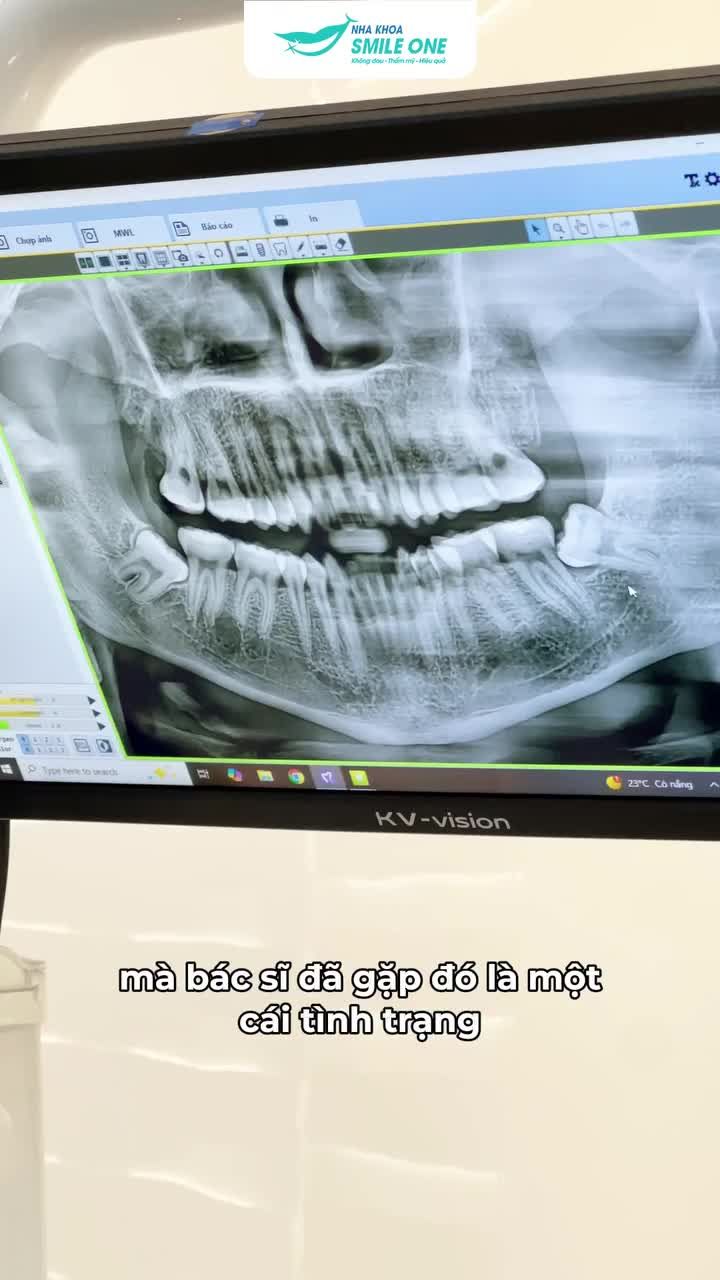

CẨN THẬN VỚI TÌNH TRẠNG RĂNG KHÔN MỌC NGẦM!

2 giờ trước

·

5 Lượt xem